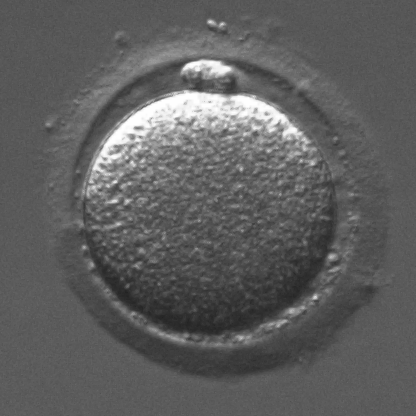

Infertility is becoming an issue for an increasing number of couples. The most common solution, in vitro fertilization, requires embryologists to carefully examine light microscopy images of human oocytes to determine their developmental potential. We propose an automatic system to improve the speed, repeatability, and accuracy of this process. We first localize individual oocytes and identify their principal components using CNN (U-Net) segmentation. Next, we calculate several descriptors based on geometry and texture. The final step is an SVM classifier. Both the segmentation and classification training is based on expert annotations. The presented approach leads to a classification accuracy of 70%.